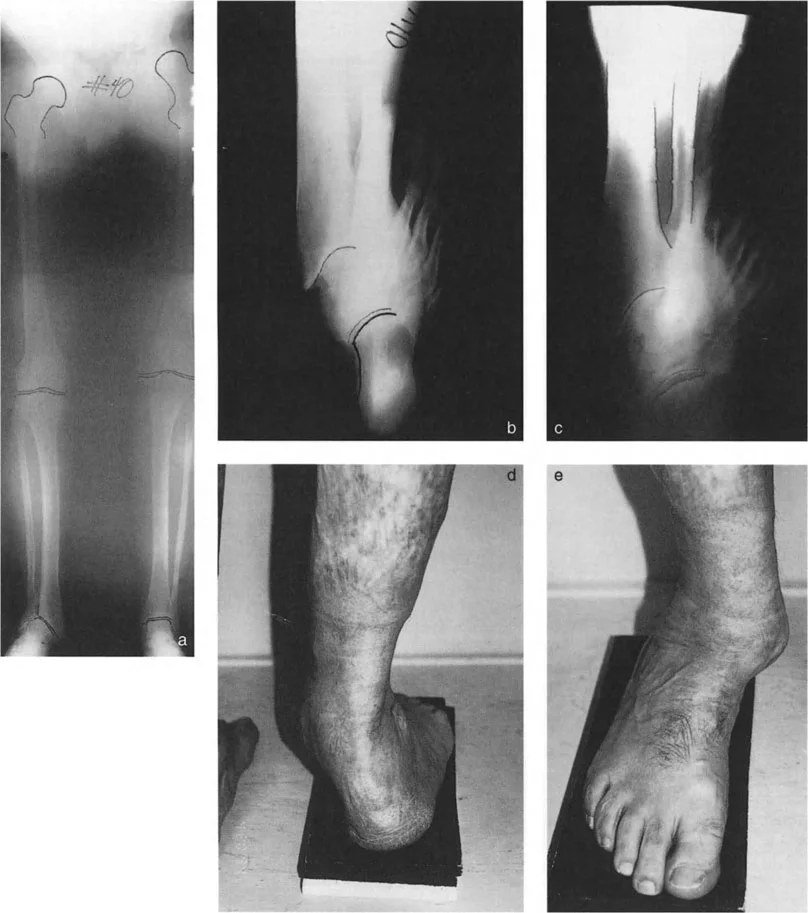

* تقييم تعويضات القدم: يتم تقييم كيف تحاول القدم تعويض التشوه في الساق. على سبيل المثال، في تشوه التقوس الساقي، قد تظهر القدم بقوس عالٍ وصلب. في تشوه الروحبة، قد تظهر القدم مسطحة ومرنة.

* الأشعة السينية (X-rays) الواقفة لكامل الطرف السفلي: هذه الأشعة ضرورية لتقييم المحاذاة الكلية للطرف السفلي تحت تأثير وزن الجسم. يطلب الأستاذ الدكتور محمد هطيف صورًا شعاعية كاملة الطول للساق أثناء الوقوف (Full-length standing alignment films) لتقييم المحور الميكانيكي للساق وتحديد زوايا المفاصل بدقة.

* الأشعة السينية الجانبية والامامية الخلفية للكاحل: تُظهر هذه الصور تفاصيل مفصل الكاحل نفسه، بما في ذلك زاوية القصبة الأمامية البعيدة (ADTA) وزاوية القصبة الوحشية البعيدة (LDTA)، وهي زوايا حاسمة لتحديد التشوه في المستويين الأمامي والسهمي.

* منظر سولتزمان (Saltzman View): هذا المنظر الإشعاعي الخاص يتم الحصول عليه بزاوية 20 درجة لقياس محاذاة عظم العقب (Calcaneus) بالنسبة لقصبة الساق، وهو أمر بالغ الأهمية لتقييم تعويضات القدم الخلفية.

صورة طبية: الاستاذ الدكتور محمد هطيف: دليل شامل لتشوهات قصبة الساق البعيدة والكاحل في صنعاء